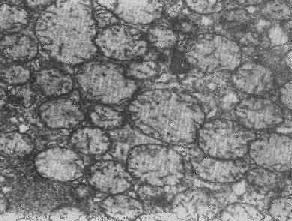

2.大小改变 细胞损伤时最常见的改变为线粒体肿大。根据线粒体的受累部位可分为基质型肿胀和嵴型肿胀二种类型,而以前者为常见。基质型肿胀时线粒体变大变圆,基质变浅、嵴变短变少甚至消失(图1-9)。在极度肿胀时,线粒体可转化为小空泡状结构(图1-10,图1-11)。此型肿胀为细胞水肿的部分改变。光学显微镜下所谓的浊肿细胞中所见的细颗粒即肿大的线粒体。嵴型肿较少见,此时的肿胀局限于嵴内隙,使扁平的嵴变成烧瓶状乃至空泡状,而基质则更显得致密。嵴型肿胀一般为可复性,但当膜的损伤加重时,可经过混合型而过渡为基质型。

图1-9 线粒体肿

图1-10肾小管上皮细胞线粒体部分空泡变

图1-11 线粒体肿胀(基质型)空泡变(心肌缺氧)